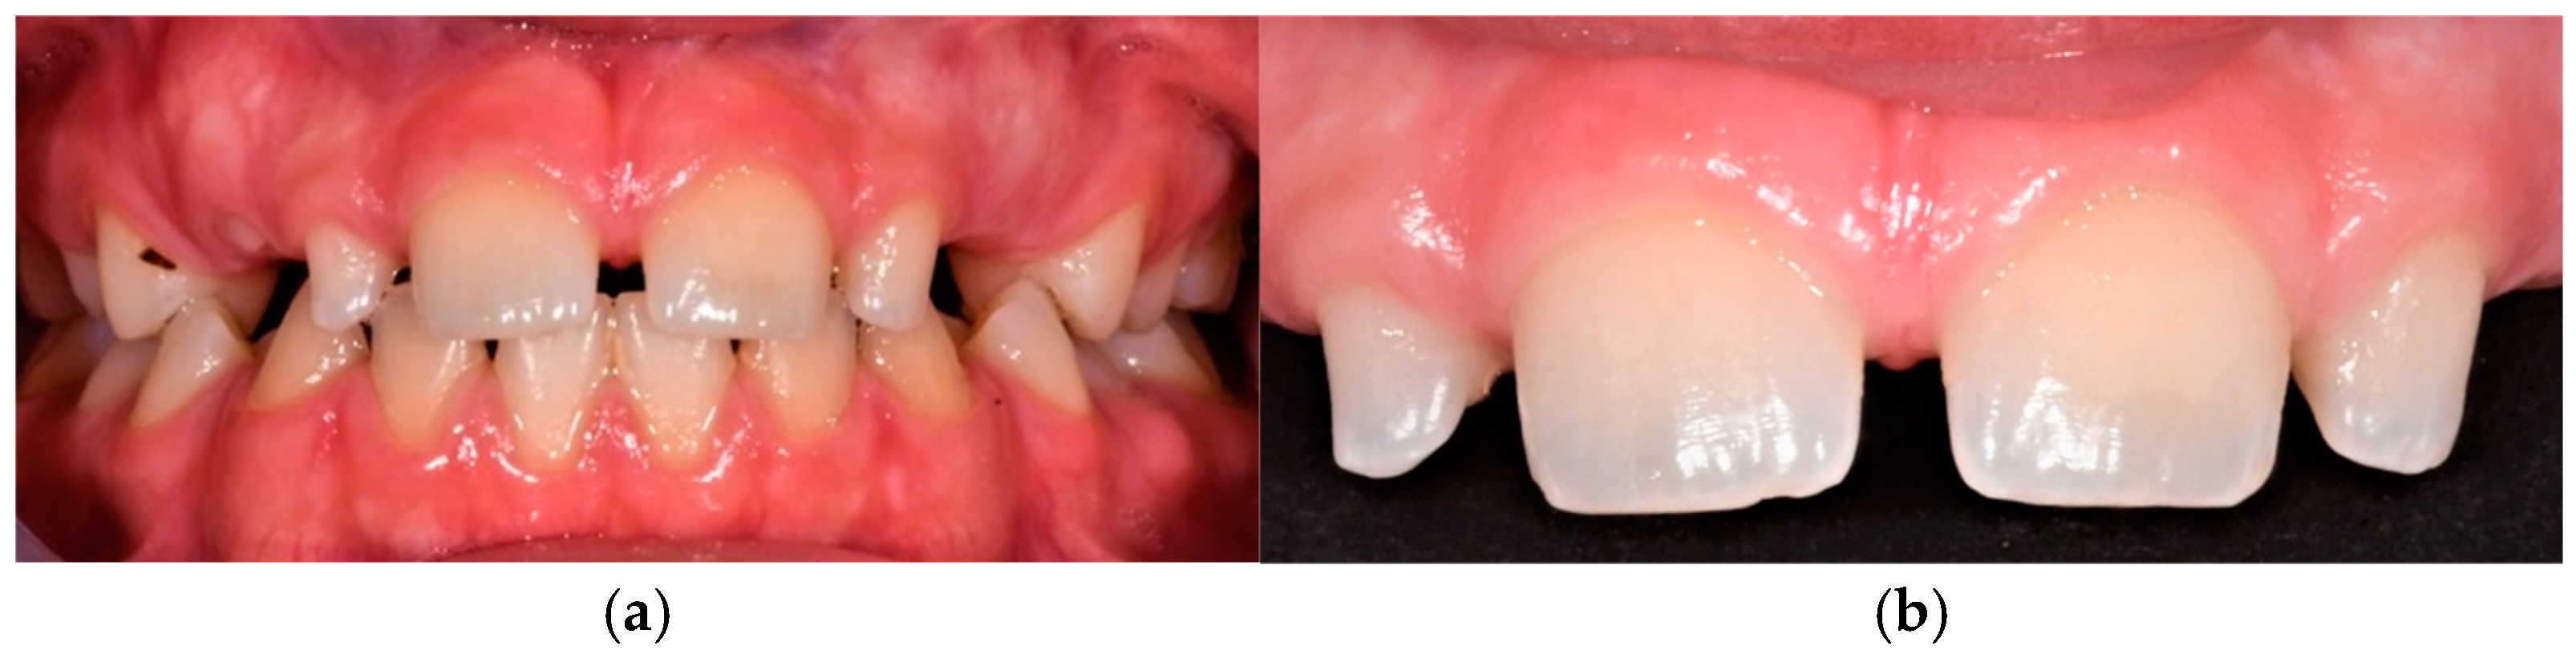

A two-year follow-up revealed excellent outcomes, with no signs of bleeding, probing depth abnormalities, occlusal issues, or changes in tooth shape or colour. The patient tolerated the procedure well (Figure 11).

Figure 11.

(a) Frontal view of final occlusion. (b) Detailed reshaping of teeth 12 and 22. (c) Occlusal view to highlight the palatal aspect of the reconstructions on 12 and 22.